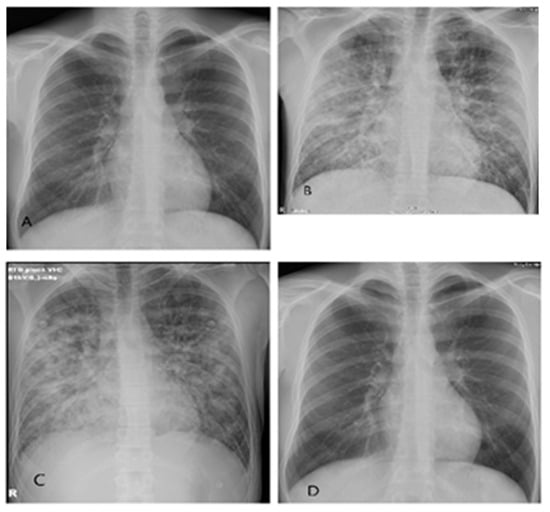

3.1. Case Report